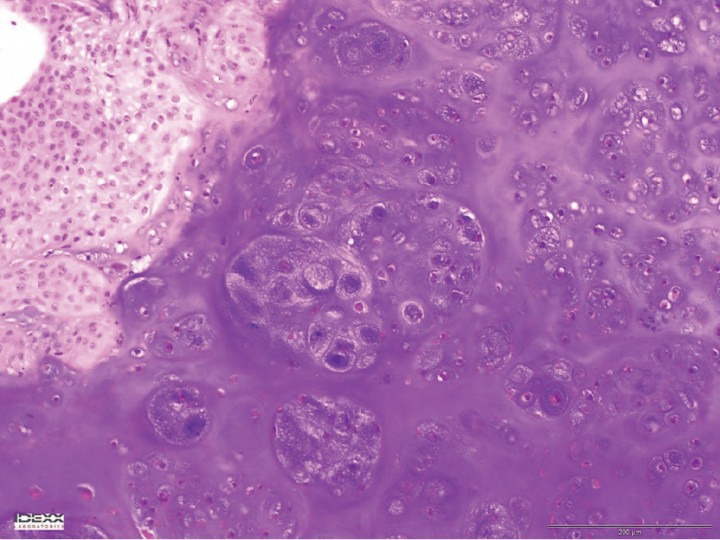

Se optó por un tratamiento quirúrgico con lobectomía del lóbulo caudal izquierdo. La histopatología confirmó la existencia de un condrosarcoma pulmonar con exéresis completa (Fig. 5).

<p>Imagen microscópica de la lesión. Se observa una proliferación de células mesenquimatosas con abundante depósito de matriz condroide, lagunas con una o varias células de redondas a estrelladas, con bordes indefinidos, citoplasma moderadamente eosinófilo, núcleo redondo, cromatina granular gruesa y nucleolo central redondo, pequeño y basófilo (tinción HE x10).</p>

Imagen microscópica de la lesión. Se observa una proliferación de células mesenquimatosas con abundante depósito de matriz condroide, lagunas con una o varias células de redondas a estrelladas, con bordes indefinidos, citoplasma moderadamente eosinófilo, núcleo redondo, cromatina granular gruesa y nucleolo central redondo, pequeño y basófilo (tinción HE x10).